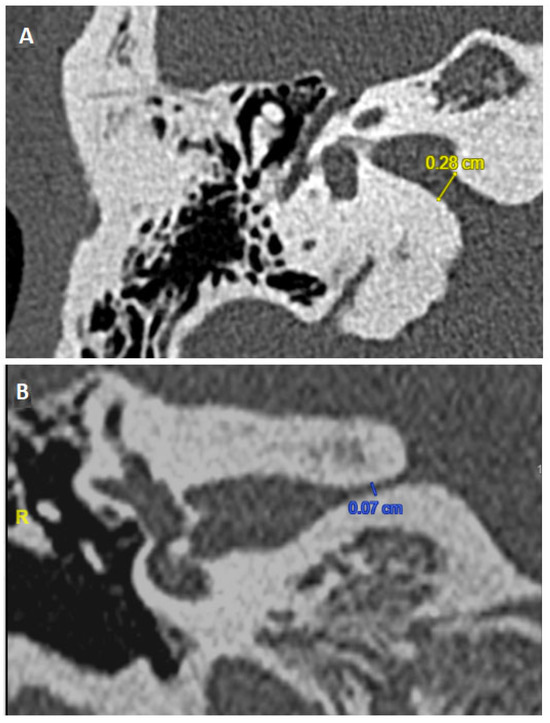

4.3. Radiological Considerations for NNIAC Diagnostic